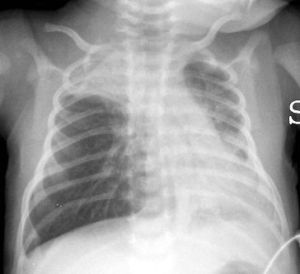

CXR of a child with RSV showing the typical bilateral perihilar fullness.

CXR demonstrating lung hyperinflation with a flattened diaphragm and bilateral atelectasis in the right apical and left basal regions in a 16-day-old infant. Note normal thymus.

- CXR

- Not routinely necessary : May lead to unnecessary use of antibiotics (atelectasis from airway plugging mimics infiltrate)

- Consider if patient is critically ill or diagnosis unclear